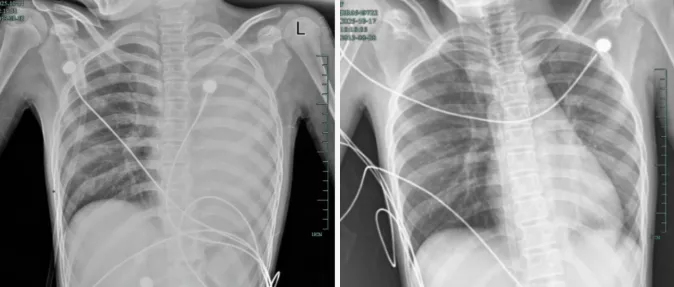

孩子感冒咳嗽看似平常,但12岁女孩笑笑(化名)的遭遇却令人胆战心惊。她仅仅发热1天,左肺就成了“白肺”,呼吸急促到无法平躺,血氧饱和度勉强维持在90%左右,情况十分危急!